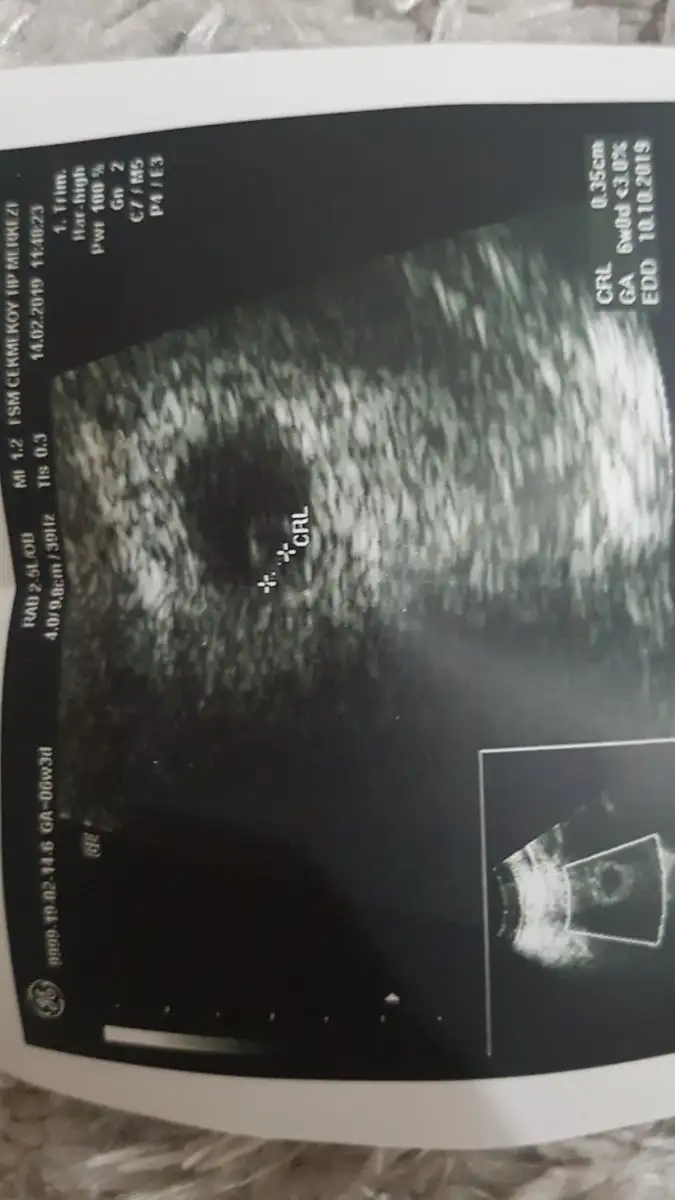

Gittim bayagi ilgili bi doktor herseyi sordu gecen haftaki ultrosan kagidima falan bakti sonra gectik karindan keseyi gorduk birazdaha bakti bebegi gordu biraz daha bakti kalp atisini gordu Allahim agliyorum sevincten kanama alanimda yok daha cok kucuk dedi 6+3 um buarada ama dedi kahve lekelerin progestan kullanmana ragmen oldugu icin dusuk tehliken var olabildigince dinlekceksin iliski yasak sanki iliskiyi kim dusunuyirsa :) ve agir kaldirmicaksin zaten yapmiyorum bunlarin hicbirini dedim

gerisi dedi yapacak bisey hamileliklerde istatiksel yuzde 10 yuzde 15 ilk haftalarda duser sagliksiz gebeliklerdir cogu dedi sen temkinini aldiktan sonra gerisi beklemektir dedi simdi hem gordum rahatladim hem dusuk tehlikem var diye uzuldum p.tesi bakalim kendi doktorum ne dicek

Usg görüntünü atsana bakım nasıl :) kız mı erkek mi diye yorumluyorlar :) Salı’yı iple cekiyorumilk miydi senin